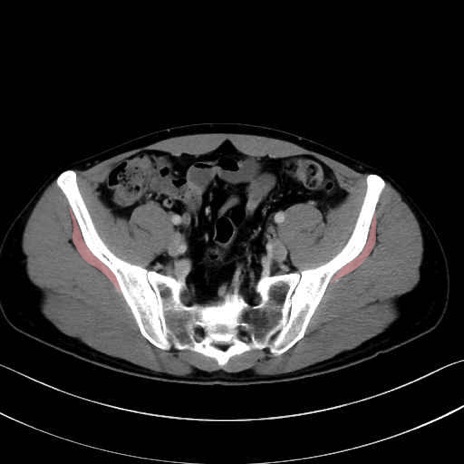

小殿筋 (Gluteus minimus)